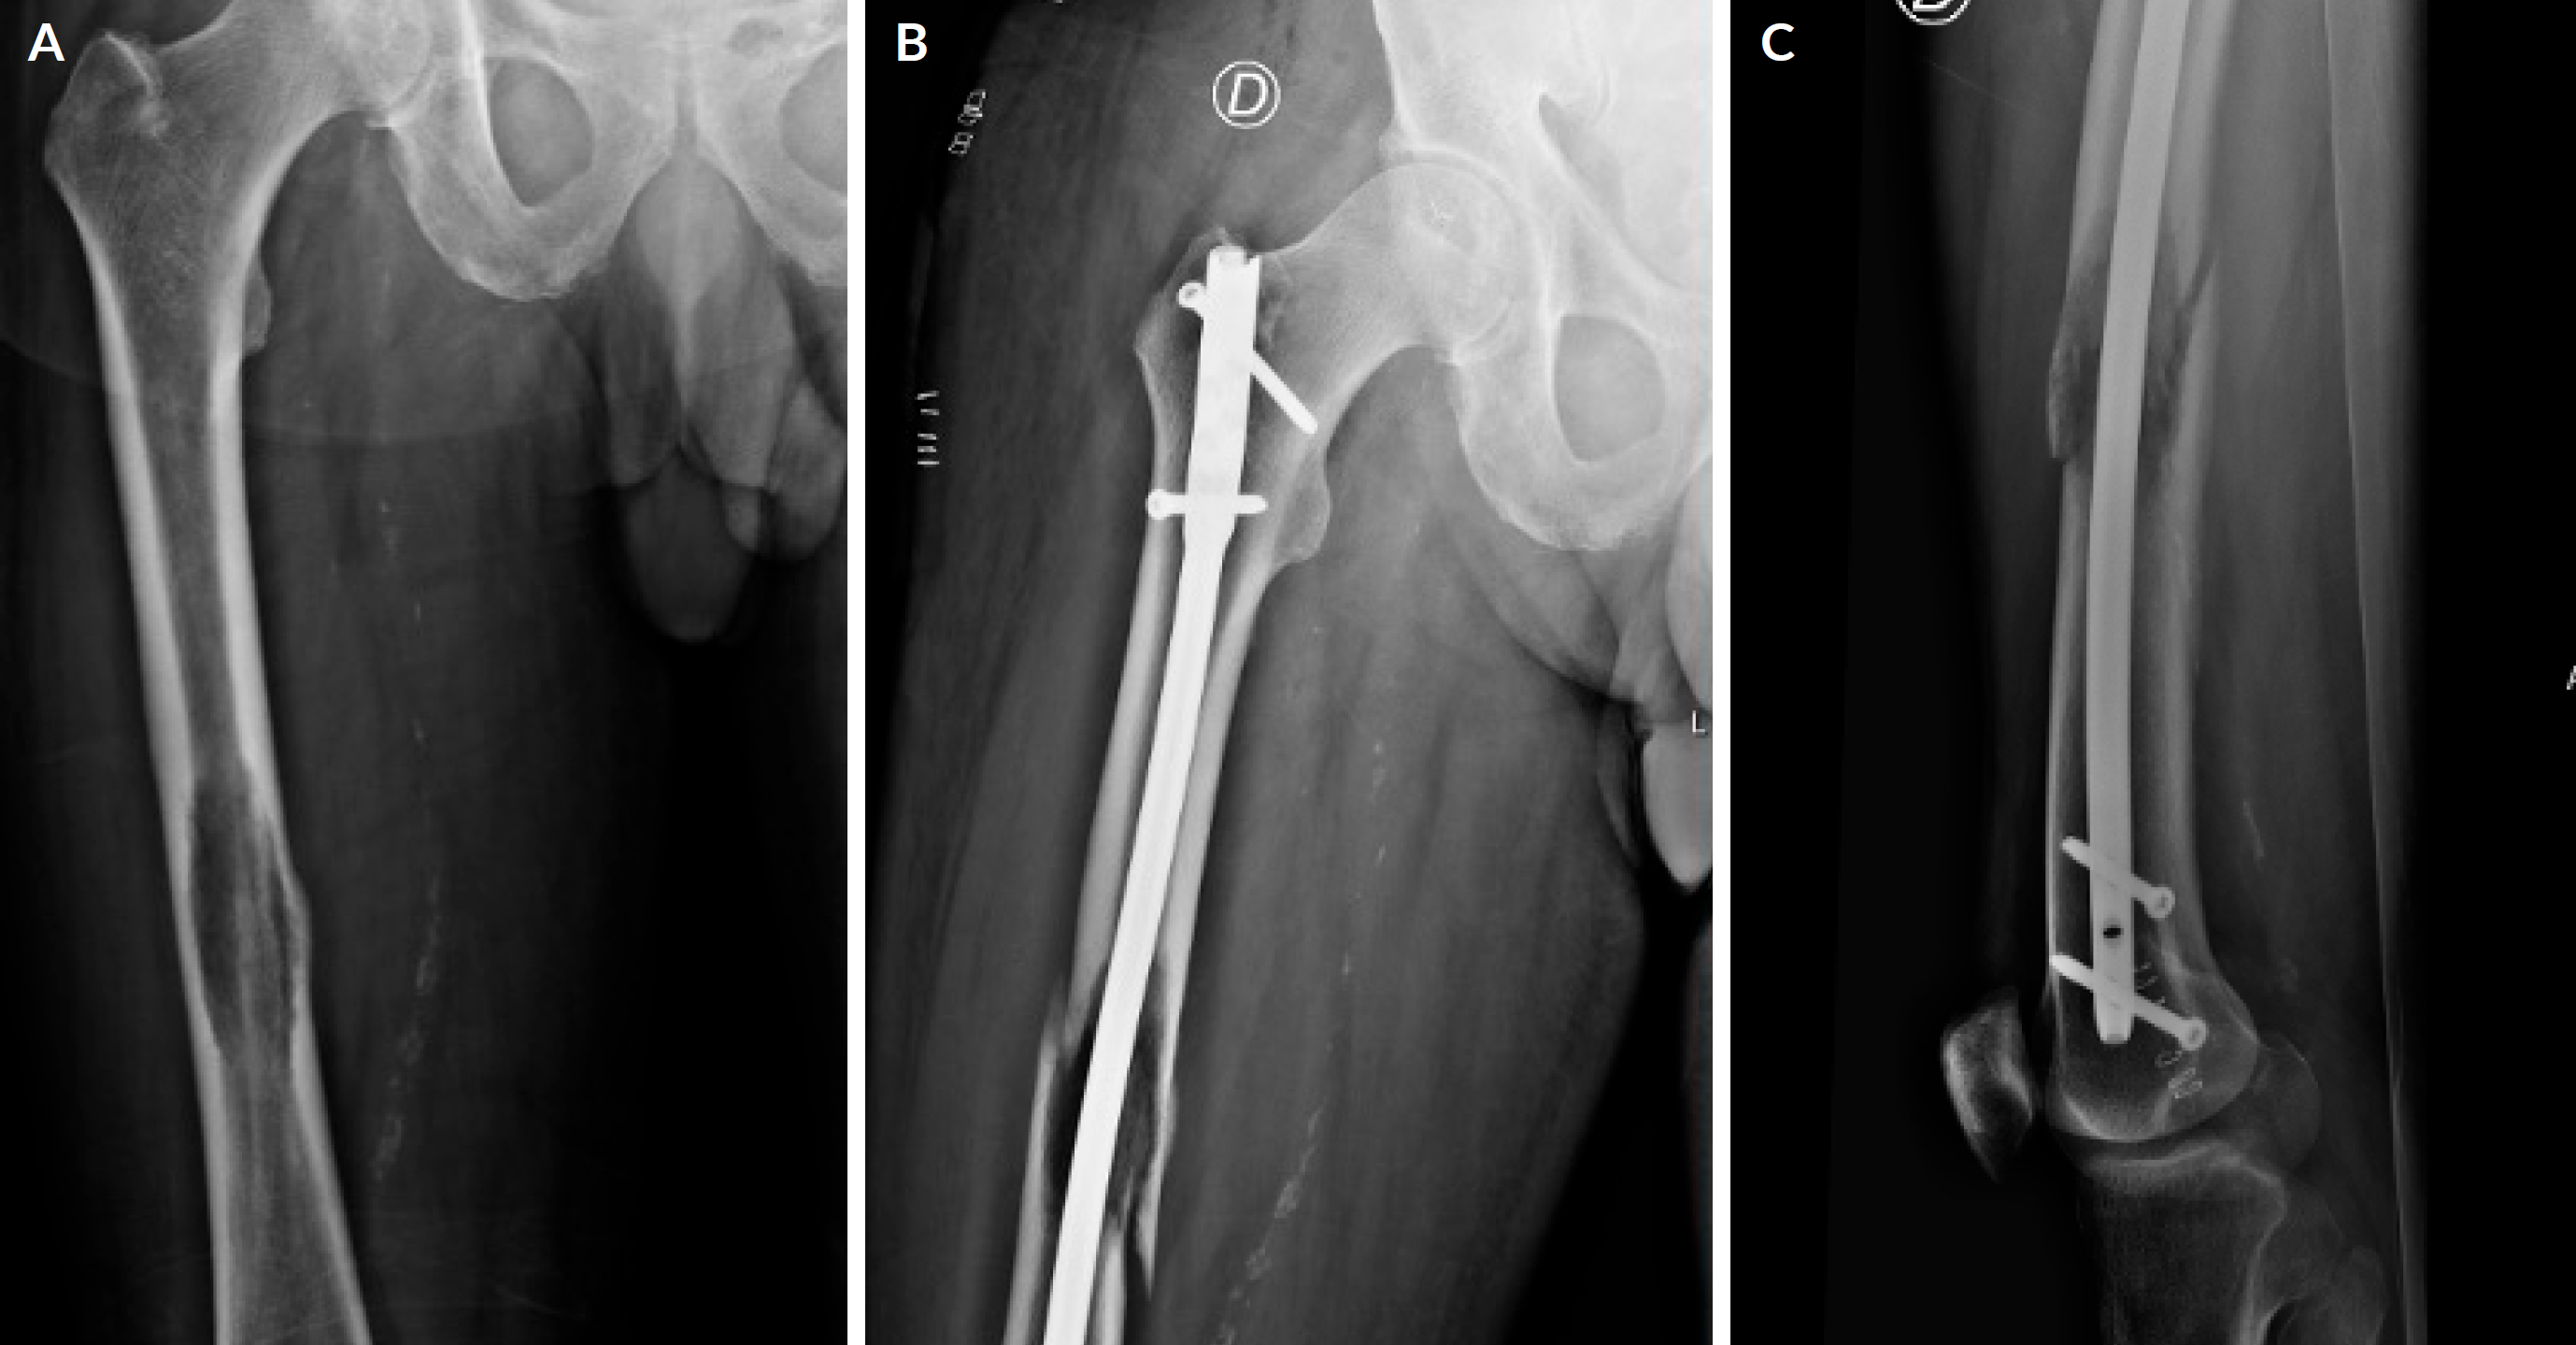

Figure 1 1A - Impending fracture of the right femoral shaft. 1B and C - Surgical stabilization of an impending fracture of the right femoral shaft with intramedullary nail.

Others may require surgical stabilization (Figs. 1A, B and C) or replacement of arthroplasty (Figs. 2A and B), especially when mechanical failures are present, such as in impending and actual fracture.13,14 In these patients, surgery aims to reduce pain, restore function, and improve quality of life.15 The type of intervention is variable and may be influenced by tumor stage, estimated patient longevity, predicted postoperative functional outcomes and the likelihood of a fracture.